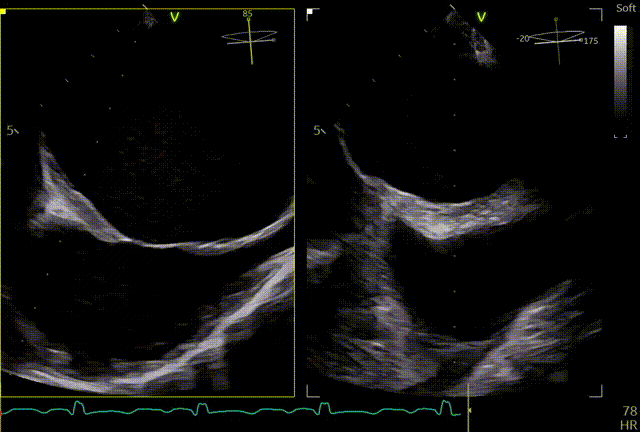

术前TTE

两腔心

短轴

四腔心zoom模式